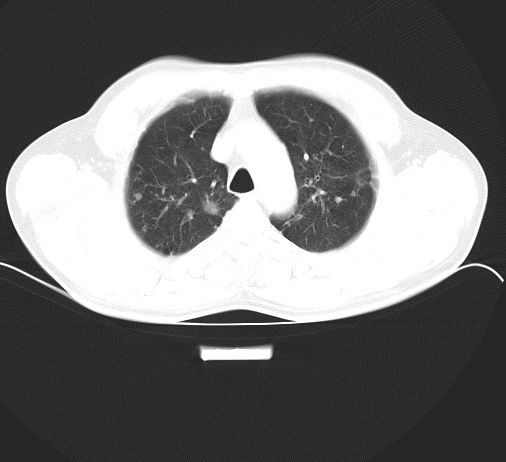

以下是引用余辉在2008-9-28 23:18:00的发言:[br]病灶多数周围性分布,肺尖分布,部分结节边缘光整,多数病灶边缘可见长棘棘影,可见多条纤维条索影,可见空洞影,右下叶背段空洞内尚可见固块内容,考虑多发结核球伴曲霉菌感染,不除外转移瘤

病灶多数周围性分布,肺尖分布,部分结节边缘光整,多数病灶边缘可见长棘棘影,可见多条纤维条索影,可见空洞影,右下叶背段空洞内尚可见固块内容,考虑多发结核球伴曲霉菌感染,不除外转移瘤